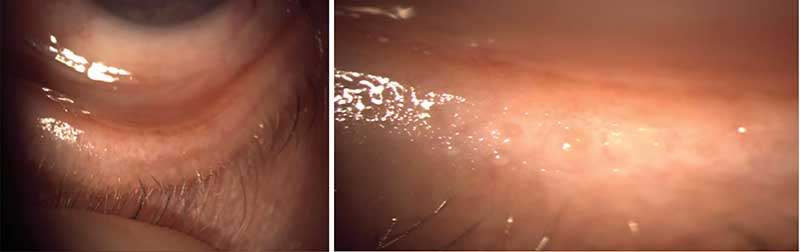

Рис. 1. Закупорка выводных протоков мейбомиевых желез при вывороте нижнего века

Мейбомиевы железы – видоизмененные голокринные сальные железы, расположенные в тарзальной пластинке века. Их отверстия находятся по краю век и выходят на поверхность глаза (рис. 1) [14]. МЖ выделяют липидно-белковую смесь (мейбум), которая выходит из их отверстий на краю века и попадает в слезную пленку при моргании. Средняя длина здоровых МЖ в верхнем веке составляет около 5,5 мм в центральной части века и около 3,5 мм в височной и носовой областях. В нижнем веке МЖ короче: их средняя длина достигает 2,0 мм в центральной части и около 1,8 мм в височной и носовой областях. Диаметр естественного отверстия МЖ около 100 мкм [15].

Наиболее распространенной формой ДМЖ является обструктивный тип, характеризующийся потерей функции МЖ вследствие закупорки их протоков (рис. 4). Следовательно, ключевым звеном патогенеза служит механическая обструкция, что определяет приоритетность мероприятий по восстановлению проходимости желез перед терапией сопутствующего воспаления [16].